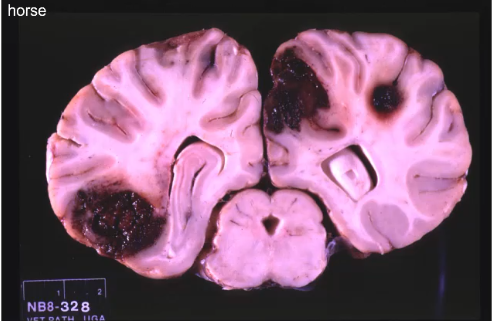

what type of hemorrhage is this?

vascular compromise (infarction)

what type of hemorhage?

-with wedge shaped lesions think vascular compromise